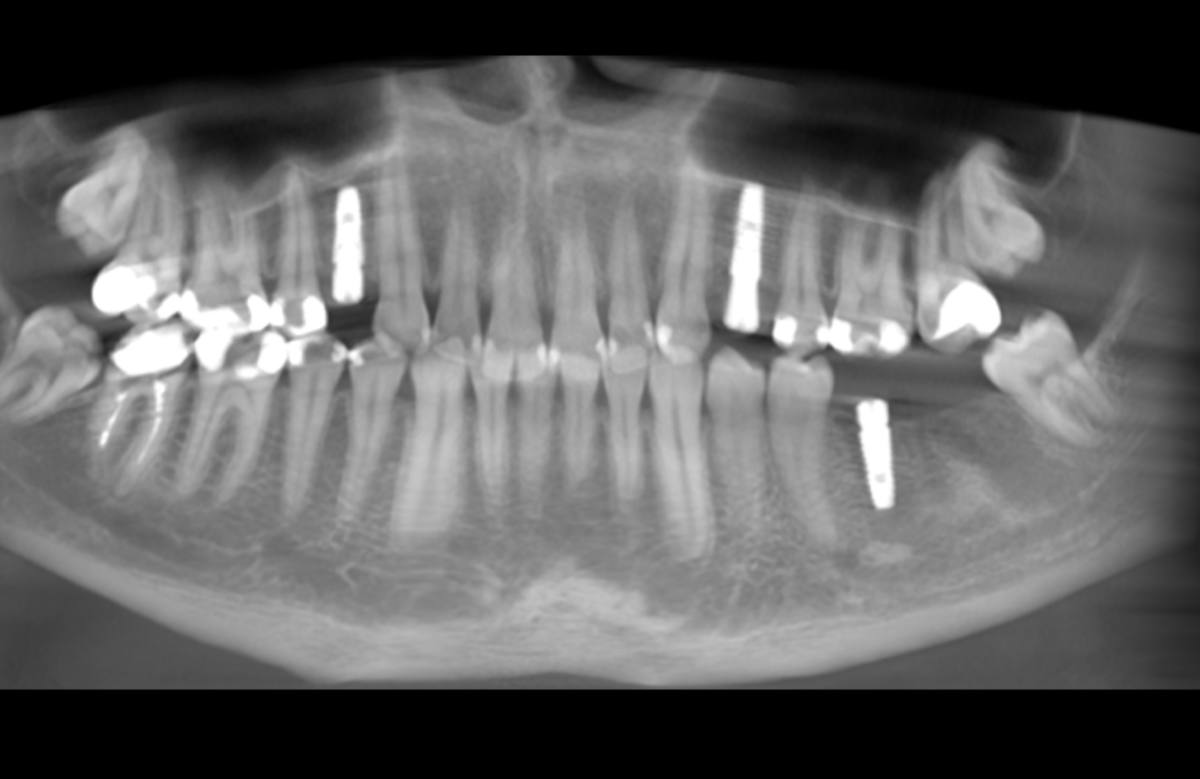

Navigovaná chirurgia, 3 implantátov

Autor práce Dr. Michal Repaši

Zubný technik Vasil Csopej